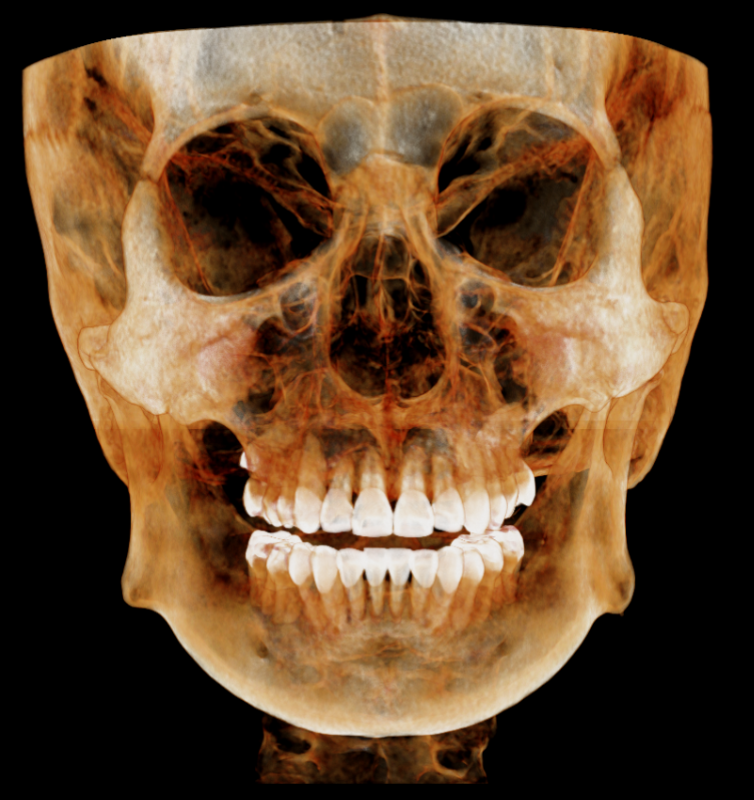

The Dentri MAX is the flagship model from HDX WILL, with the largest avail max FOV at 18x16.5, suitable for a wide scope of uses including advanced implantology, endodontics, orthodontics, orthognathic, bilateral TMJ & airway studies.